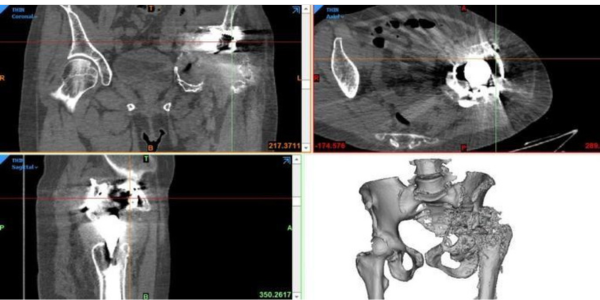

In this case study, we present a case of female patient aged 60 years who had to undergo a 3rd revision

surgery because of the inability to walk and unbearable pain in her lower limb due to previous surgeries which was treated with 3D printed customized hip implant.

- Badly damaged pelvic bone because of three previous surgeries

- No support to fix the acetabulum

- Broken implant in the pelvis

- Close to important pelvic organs

- Huge defect required proper assessment